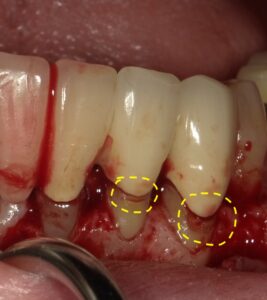

画像の一番右端の歯が縁下カリエスになっています。

レントゲンでは黄色に囲った部分が虫歯になっています。

フラップ手術で歯茎を開くと黄色で囲った部分が

虫歯になっています。

樹脂で充填する治療を行いました。